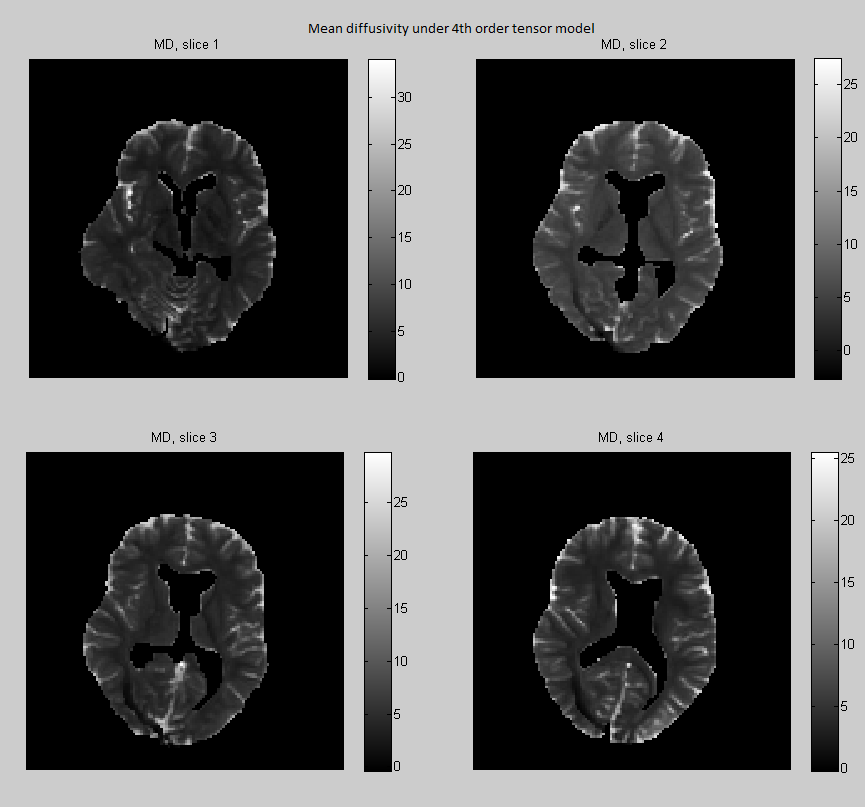

Fractional anisotropy (FA) measures the degree of anisotropy, while mean diffusivity (MD) is the average of the diffusivity function over the unit sphere. Both measures are used as biomarkers to study brain pathologies. These quantities are expressed in terms of the eigenvalues of the 2nd order tensor as

In Section 3.9 we have seen that there is a linear bijection between the tensor coefficients and the coefficients of the truncated spherical harmonic expansion of the diffusivity. This implies that we can map linearly a 4th-order tensor to a 2nd-order tensor as follows (see Özarslan E., Mareci T.H. (2003)):

and the mean diffusivity can be also expressed in terms of the 4th order tensor coefficients as

| (4.26) |

where was defined in Eq. (3.18). In Fig. 11 and 12 we compare the respectively the Bayesian estimates of FA and MD derived under the 2nd and 4th-order tensor models.